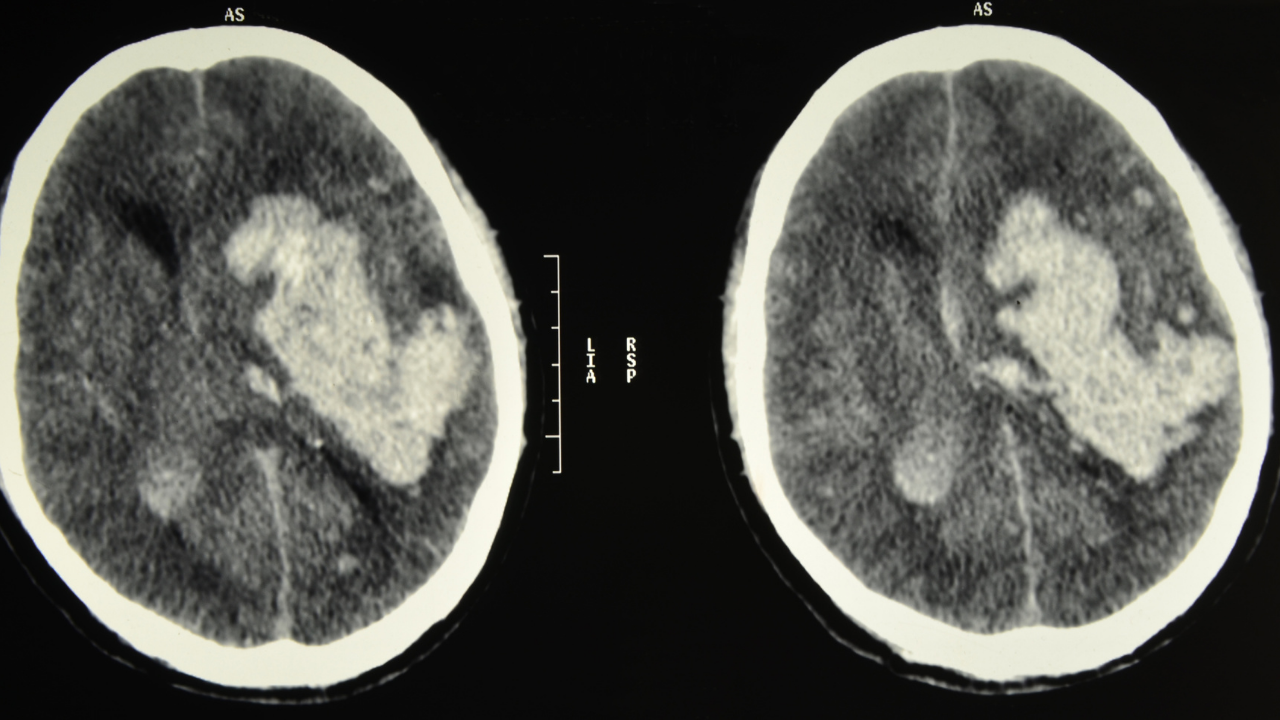

Kalp durması sonrası yaşanan “ölüme yakın deneyimler”, bazı kişilerin bilinçli deneyimlerini beyin aktivitesi tamamen durduktan sonra yaşadıklarını öne sürüyor.

Örneğin, bazı ameliyatlarda beyin aktivitesi sıfıra inmişken bile hastalar daha sonra yaşadıkları bir "aydınlanma" veya "beden dışı gözlem" durumunu anlatıyor.

Bu da şu soruyu getiriyor:

"Bilinç beyin dursa da kalmaya devam mı ediyor?"